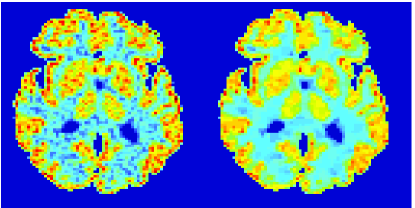

In the images shown in the figures we illustrate the calculated uptake rates of the FDG. Images for the CMRGlc can be obtained by directly scaling . In figure 1 we compare the result of using Patlak and TV-Patlak for estimating the uptake rates with respect to no noise, noise in the input function, Poisson noise in the sinogram, and finally with respect to the case in which the irreversibility assumption is violated but without noise in the sinogram or input data. In each case the histogram of the relative errors is given on the left, the Patlak image in the middle and the TV-Patlak on the right. The different scales in the histograms are due to the total number of results illustrated. When there is no noise (triples and ) the histogram illustrates results over all voxels but only one simulation, while for the noisy simulations the results are for all voxels over all realizations of the noise. The TV-Patlak images are more homogeneous in all cases and the relative errors are smaller. The figures clearly show the improvements of employing the TV-Patlak method as compared to using Patlak independently for each voxel. This is confirmed in figure 2 in which images with noise in the sinogram, positive and different noise levels in the input function are shown.